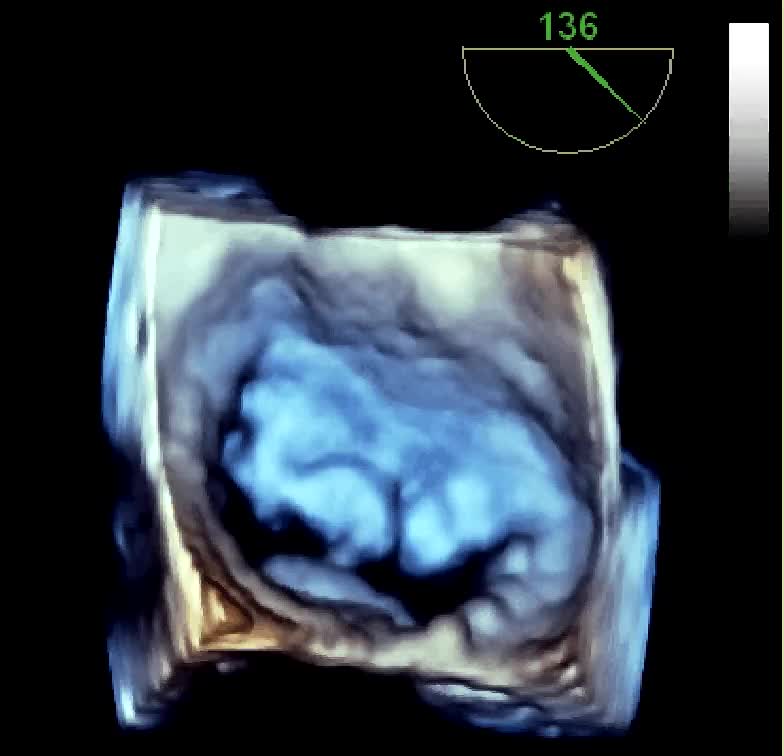

Insufficienza mitralica da rottura cordale

Autore:

Daniela Torta